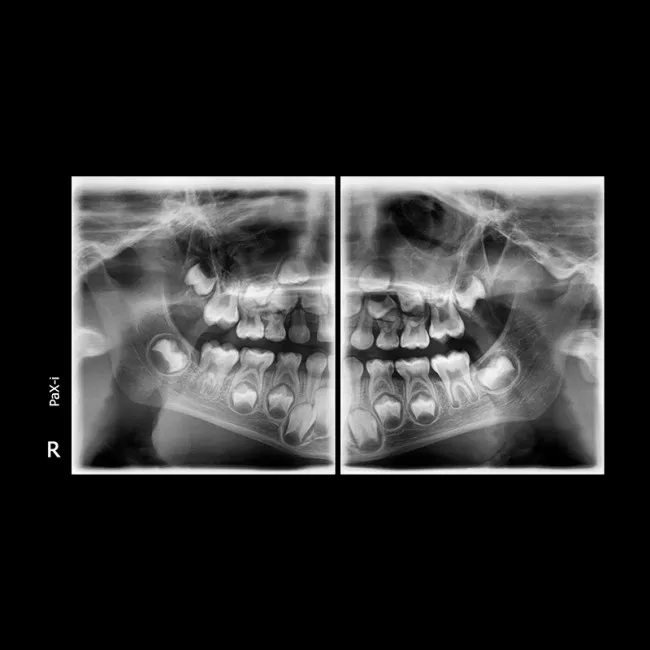

Полное изображение зубочелюстной системы Ортопантомограф предоставляет полную картину состояния зубов, челюстей, суставов и окружающих тканей. Это особенно полезно для выявления заболеваний, таких как кисты, опухоли, воспаления и повреждения челюстей.

Высокая точность и подробность снимков ОПТГ предоставляет детализированные изображения, что помогает врачу точно определить наличие заболеваний и планировать лечение. Снимки могут быть использованы для диагностики заболеваний, таких как кариес, пародонтит, а также для оценки состояния имплантатов и ортодонтических конструкций.

Общие обследования ОПТГ используется для общего обследования состояния зубочелюстной системы, выявления скрытых заболеваний или изменений, которые невозможно обнаружить при обычном осмотре.

Диагностика заболеваний С помощью ОПТГ можно диагностировать такие заболевания, как кариес, пародонтоз, заболевания челюстных суставов, а также обнаружить опухоли и воспалительные процессы.